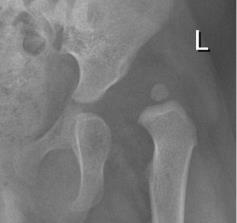

Segmentation example showing the outline of the proximal femur of a 2-year-old and an 18-year-old as well as the outline of the pelvis. Our BoneFinder® module achieved an average point-to-curve-error of 1mm and a point-to-curve-error of less than 2mm for 95% of all 450 images.

Segmentation example showing the outline of a children's proximal femur. Our BoneFinder® module achieved a point-to-curve-error of less than 4% of the femoral shaft width for 95% of all 1179 images.